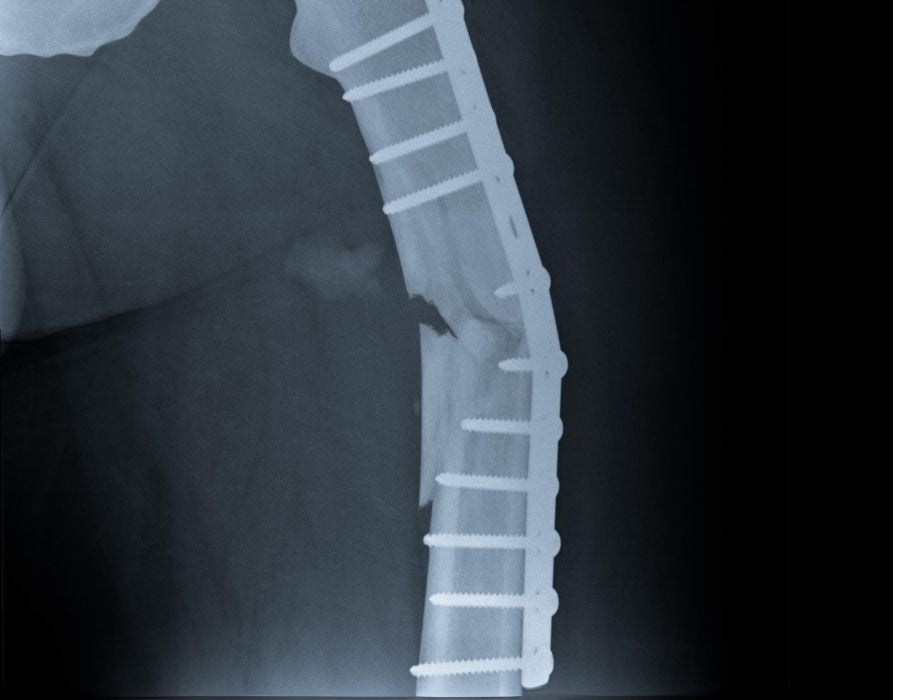

One day, while watering her roses, Edith tripped over a loose cobblestone and fell, breaking her hip. It was a small and relatively insignificant fall, but the damage to her body was significant.

Edith, who had always been the life of the party and the family's rock, now found herself stuck in bed, needing help with everything. The recovery was slow and full of setbacks. The vibrant lady who used to run around the house was now often seen looking out the window, missing her garden and kitchen.

That simple fall, what seemed just a moment's misstep, had a profound impact on Edith's life. Instead of days filled with gardening and baking, she faced long, tough periods of recovery that seemed to stretch on without much hope for return to her old joys. The lively home atmosphere, once brimming with the scent of pies and laughter, turned quiet and somber. Edith, who had always been the heart and soul of her family, now felt like she was watching life go by from the sidelines.

This fall didn't just break her hip; it broke her spirit too. It was a harsh reminder of how quickly things can change, leaving her and her family to navigate a new reality far removed from the vibrant life they were used to.